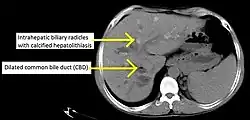

Historically, a cholangiogram would be obtained via endoscopic retrograde cholangiopancreatography (ERCP), which typically reveals "beading" (alternating strictures and dilation) of the bile ducts inside and/or outside the liver. Currently, the preferred option for diagnostic cholangiography, given its noninvasive yet highly accurate nature, is magnetic resonance cholangiopancreatography (MRCP), a magnetic resonance imaging technique. MRCP has unique strengths, including high spatial resolution, and can even be used to visualize the biliary tract of small animal models of PSC.[22]